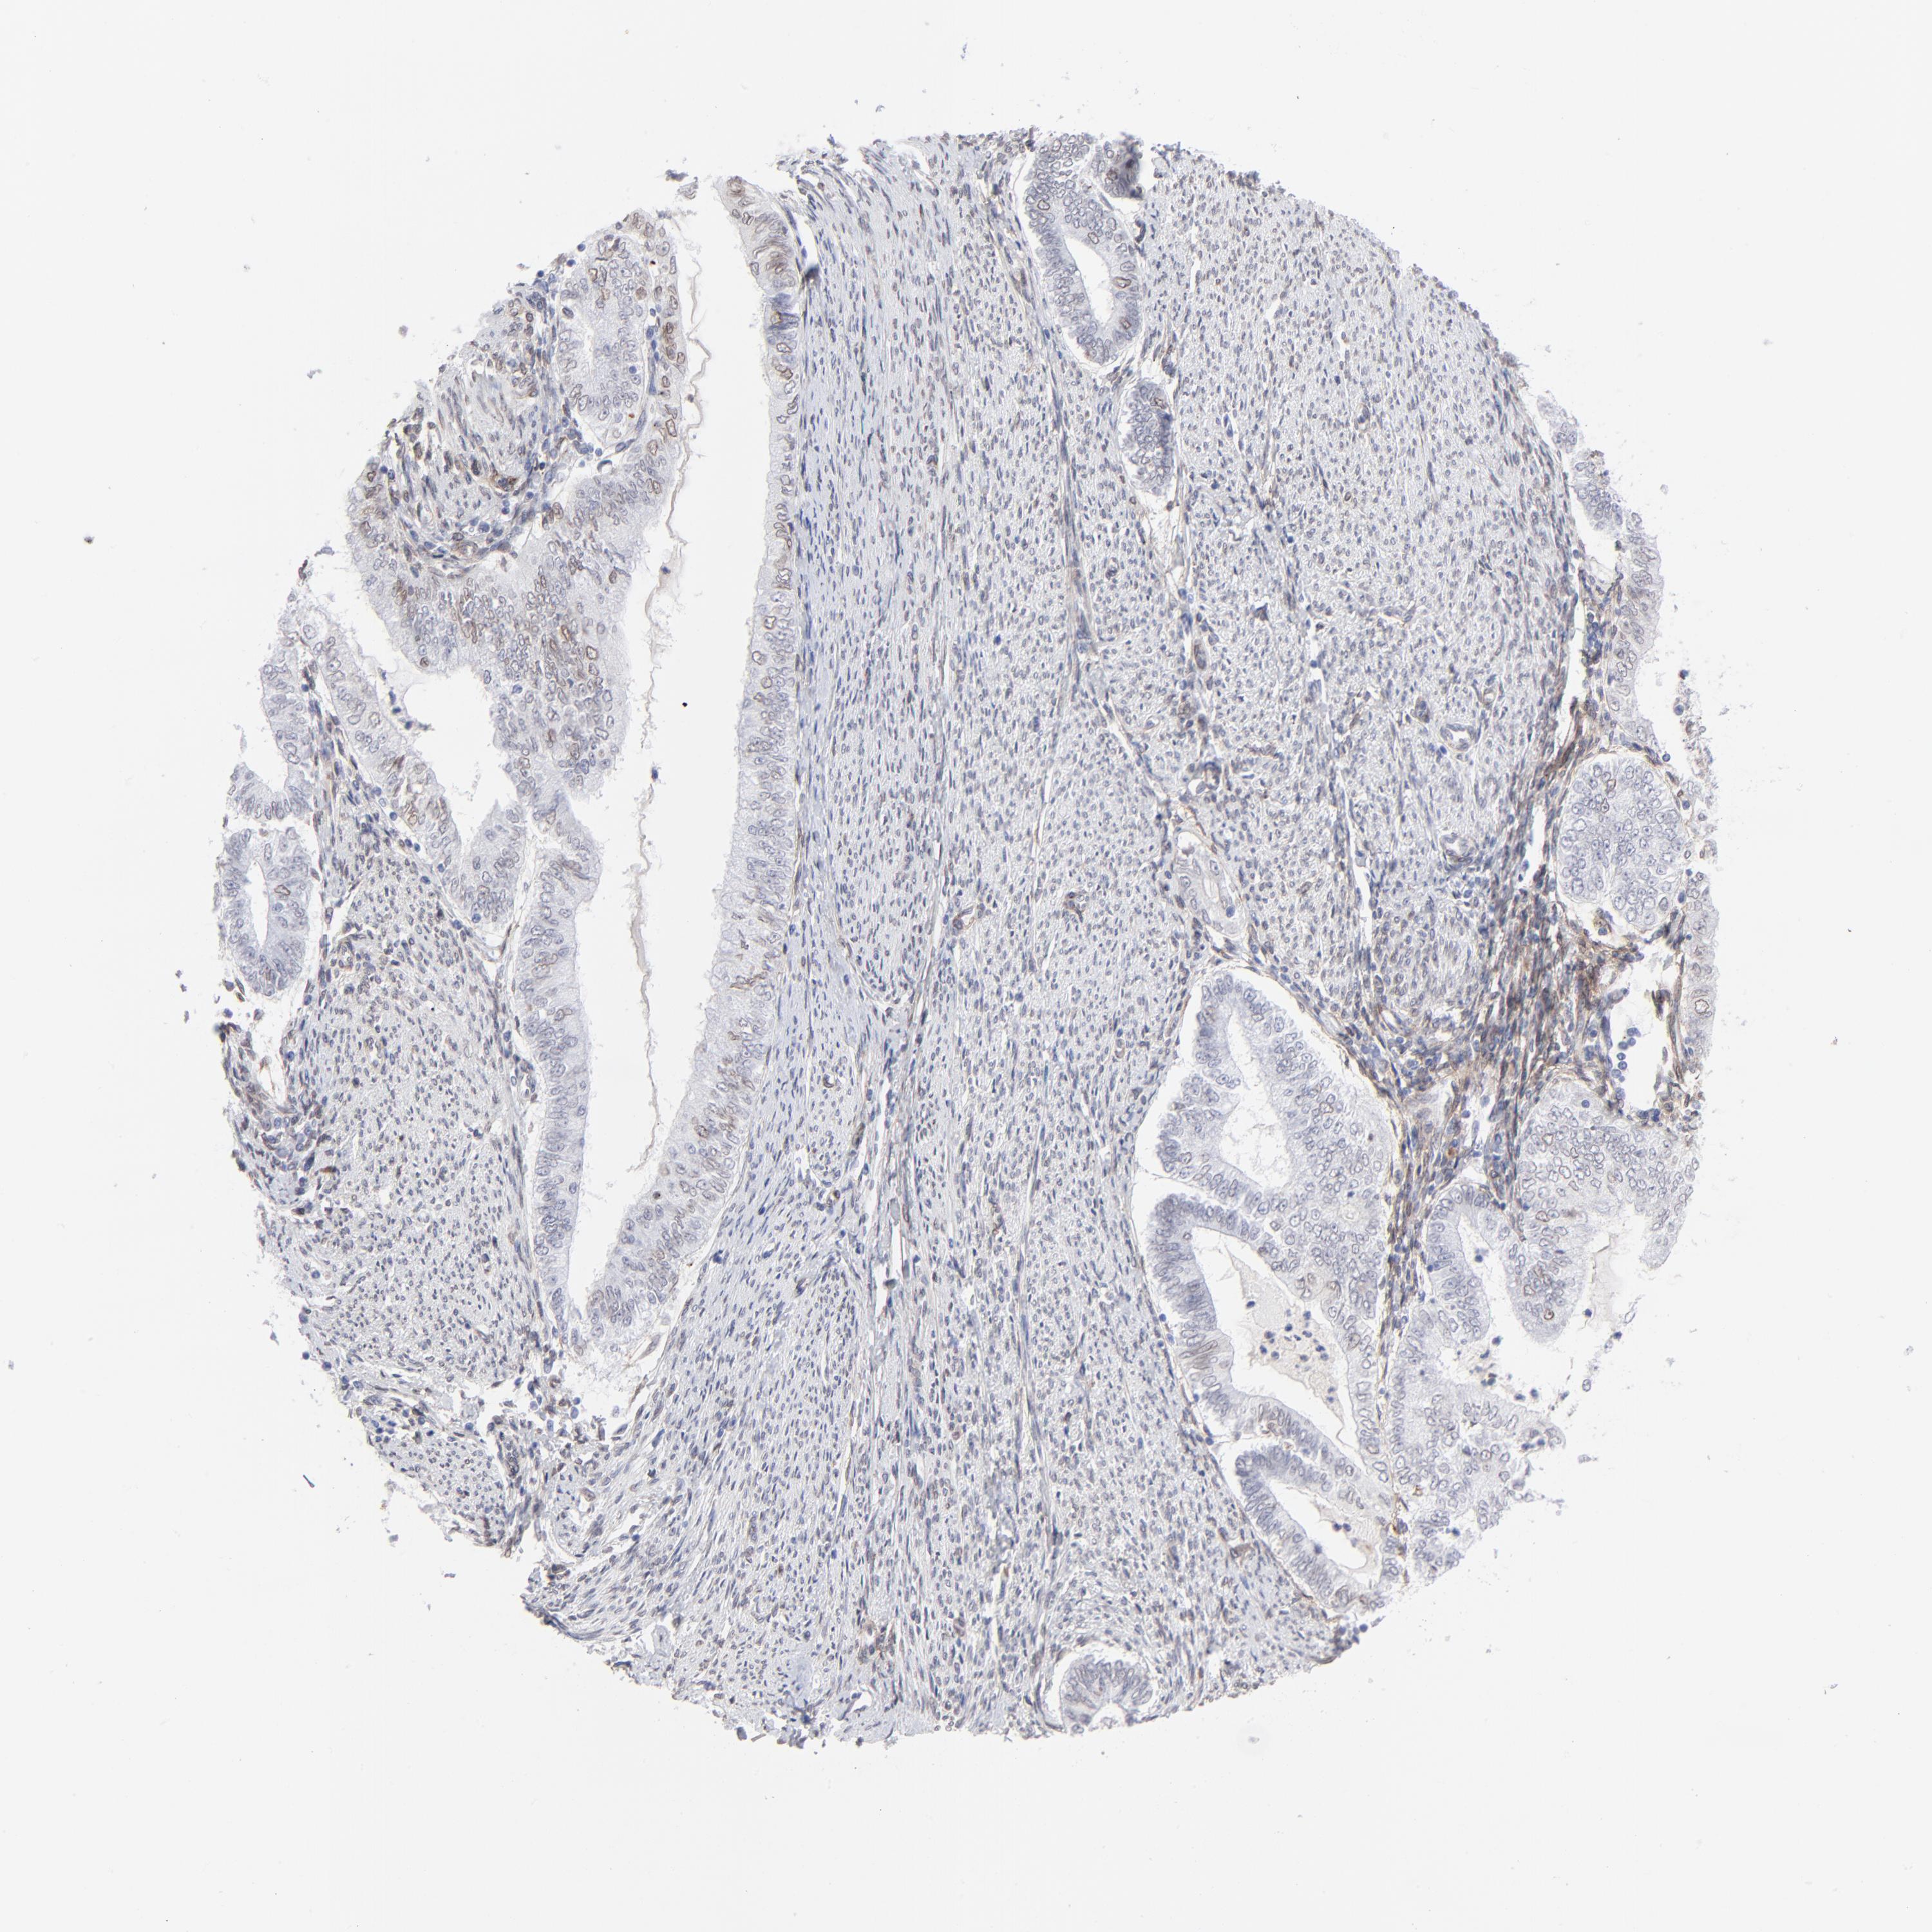

ENDOMETRIAL CANCER - Protein expressioni

A mouse-over function shows sample information and annotation data. Click on an image to view it in a full screen mode. Samples can be filtered based on level of antibody staining by selecting one or several of the following categories: high, medium, low and not detected. The assay and annotation is described here.

Note that samples used for immunohistochemistry by the Human Protein Atlas do not correspond to samples in the TCGA dataset.

Antibody stainingi

Antibody staining in the annotated cell types in the current human tissue is reported as not detected, low, medium, or high, based on conventional immunohistochemistry profiling in selected tissues. This score is based on the combination of the staining intensity and fraction of stained cells.

Each image is clickable and will lead to virtual microscopy that enables deeper exploration of all samples and also displays staining intensity scores, fraction scores and subcellular localization as well as patient and tissue information for each sample.

Antibody CAB003842

Antibody CAB018144

Staining

High

Medium

Low

Not detected

Intensity

Strong

Moderate

Weak

Negative

Quantity

>75%

75%-25%

<25%

None

Location

Nuclear

Cytoplasmic/membranous

Cytoplasmic/membranous,nuclear

Adenocarcinoma, NOS

Neoplasm, malignant, NOS

Adenoma, NOS